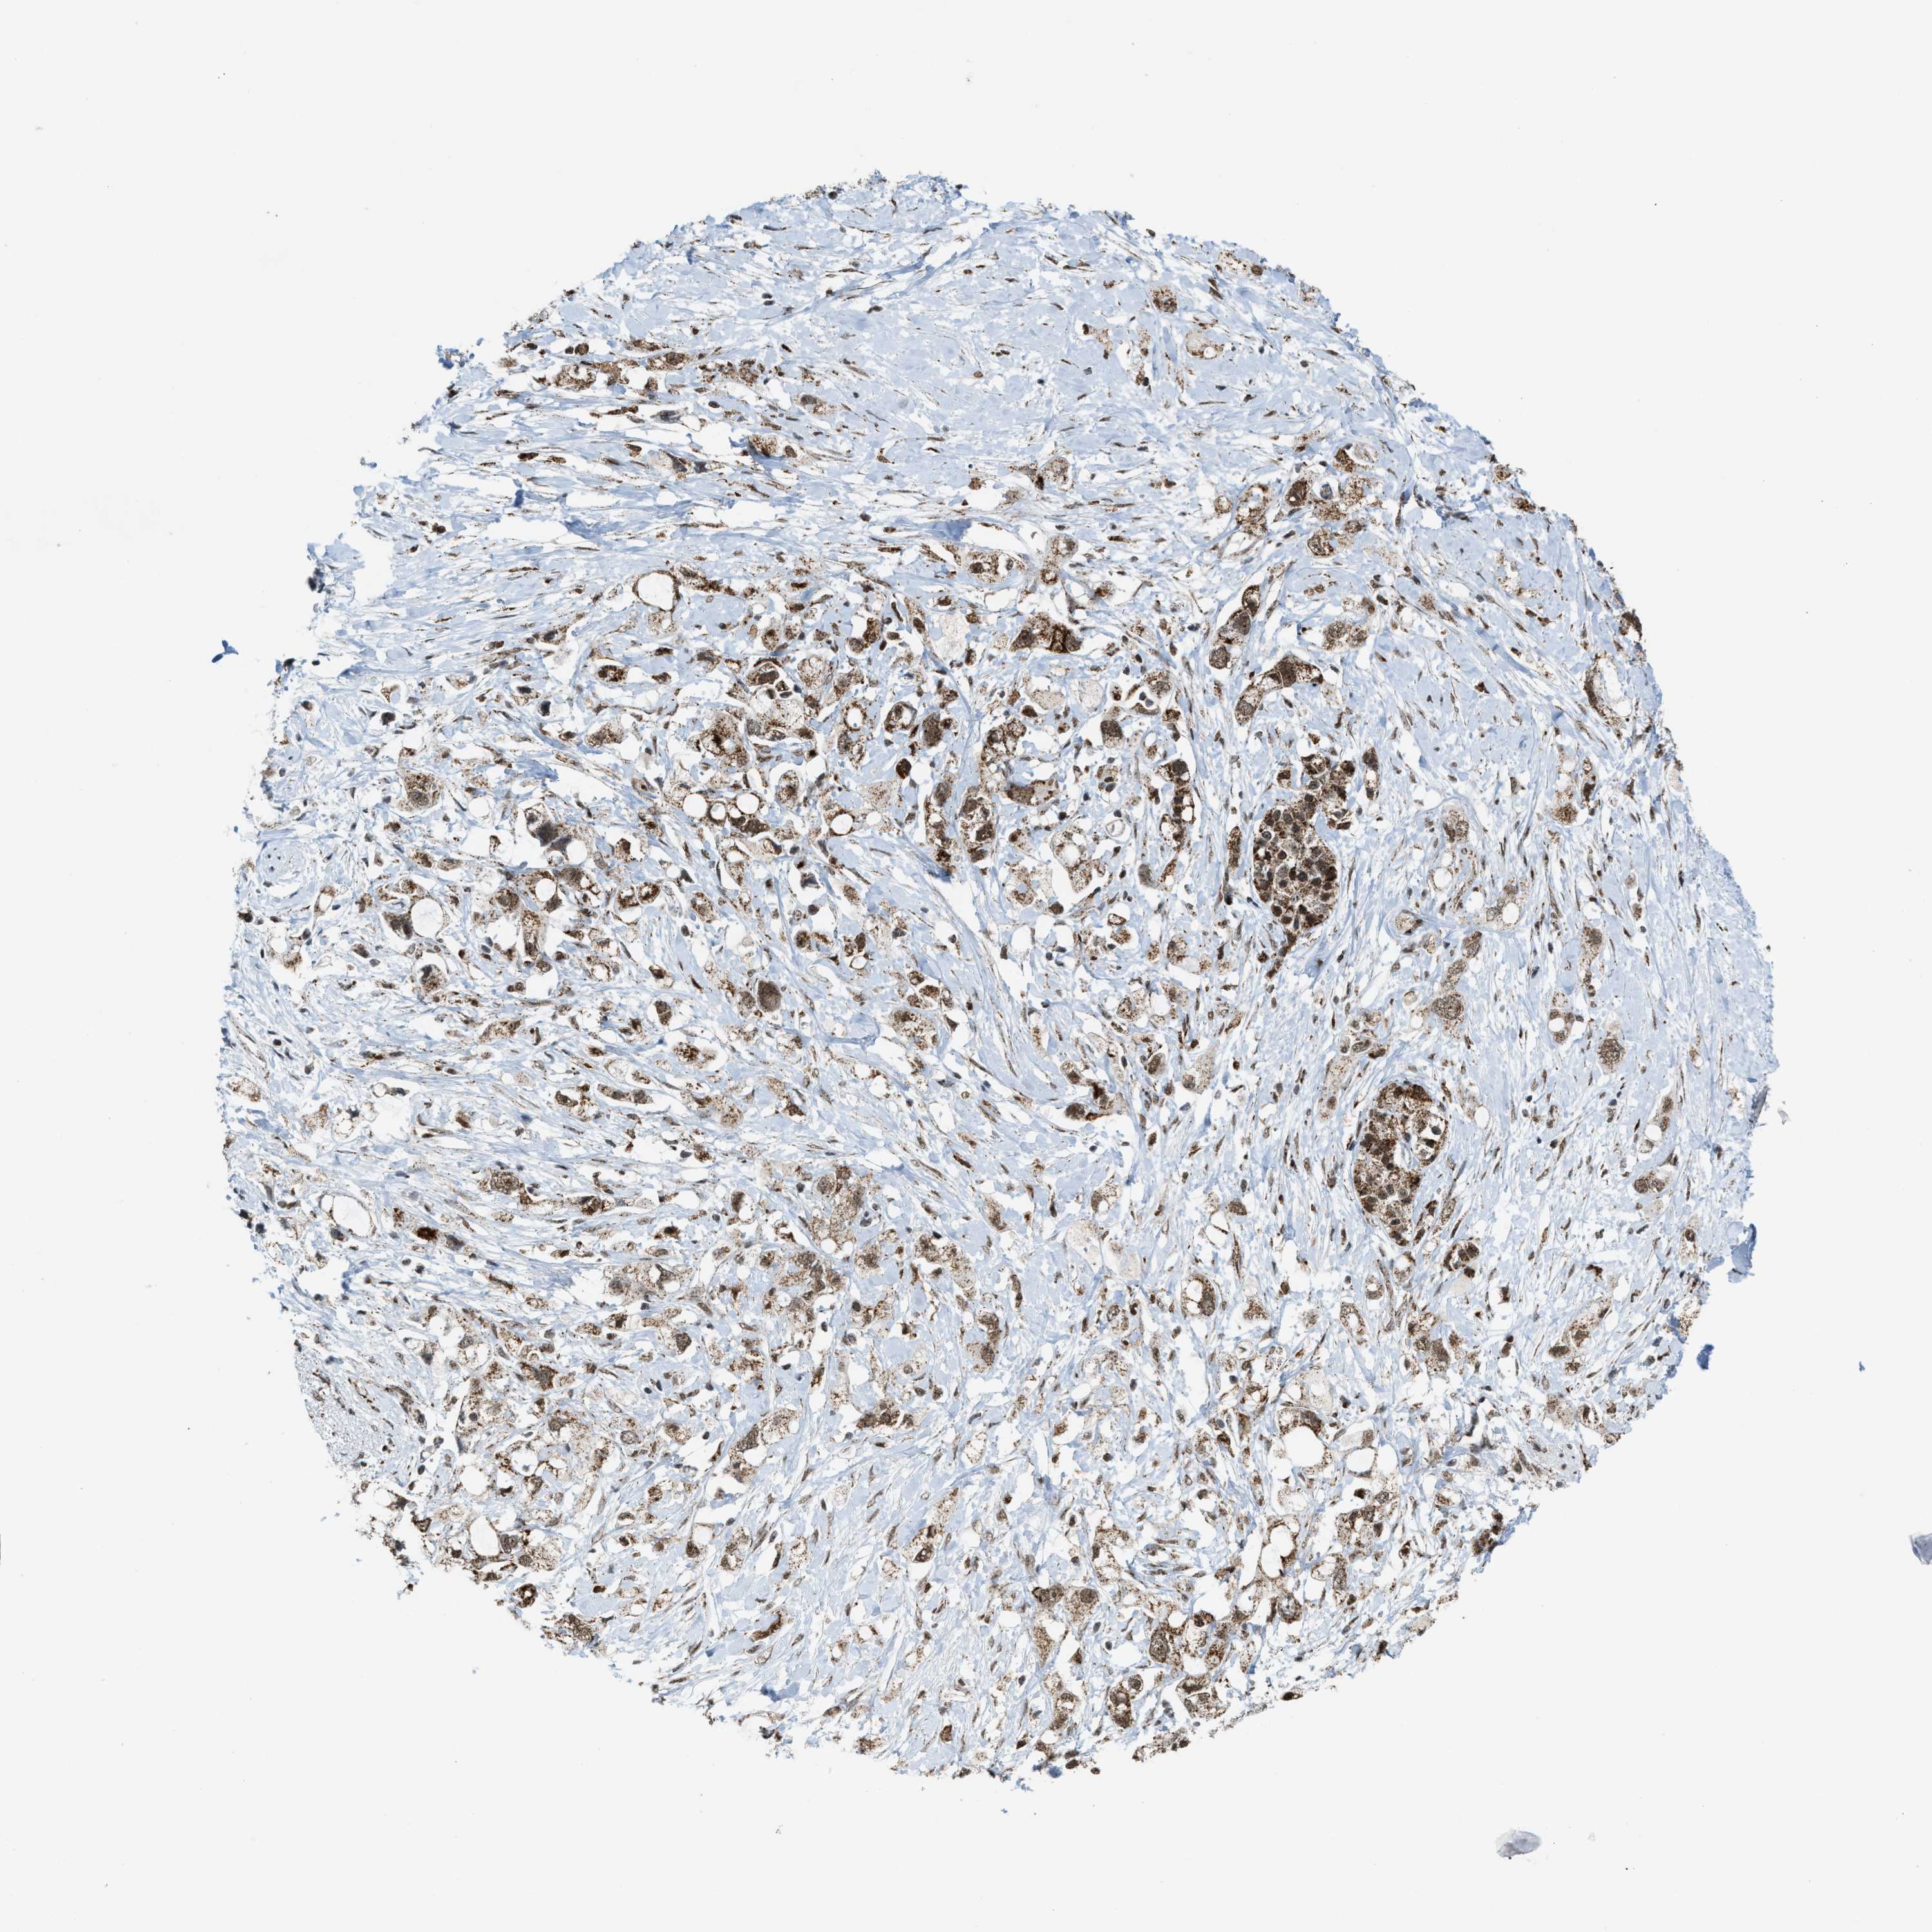

PANCREATIC CANCER - Protein expressioni

A mouse-over function shows sample information and annotation data. Click on an image to view it in a full screen mode. Samples can be filtered based on level of antibody staining by selecting one or several of the following categories: high, medium, low and not detected. The assay and annotation is described here.

Note that samples used for immunohistochemistry by the Human Protein Atlas do not correspond to samples in the TCGA dataset.

Antibody stainingi

Antibody staining in the annotated cell types in the current human tissue is reported as not detected, low, medium, or high, based on conventional immunohistochemistry profiling in selected tissues. This score is based on the combination of the staining intensity and fraction of stained cells.

Each image is clickable and will lead to virtual microscopy that enables deeper exploration of all samples and also displays staining intensity scores, fraction scores and subcellular localization as well as patient and tissue information for each sample.

Antibody HPA019522

Antibody HPA021002

Staining

High

Medium

Low

Not detected

Intensity

Strong

Moderate

Weak

Negative

Quantity

>75%

75%-25%

<25%

None

Location

Nuclear

Cytoplasmic/membranous

Cytoplasmic/membranous,nuclear

Adenocarcinoma, NOS